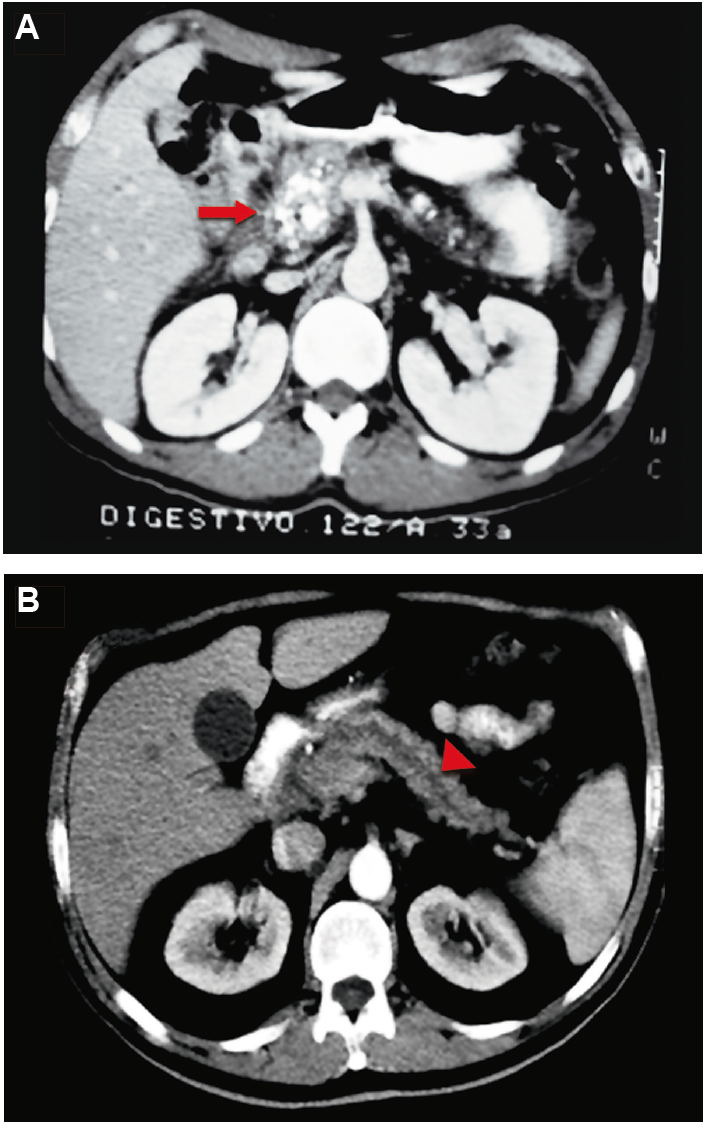

Figura 2. Tomografía computada que demuestra las alteraciones morfológicas

características para la indicación de este procedimiento. A: Cabeza de páncreas

aumentada de tamaño con cálculos intraductales e impactados en los canalículos periféricos y en el

parénquima. B: dilatación del conducto pancreático principal (Wirsung) del cuerpo y

cola.

Se indicó la OF en los pacientes con masa a nivel de la cabeza del páncreas y dilatación del conducto de Wirsung mayor de 6 mm, con DA intratable con analgésicos no opioides (Figura 2).